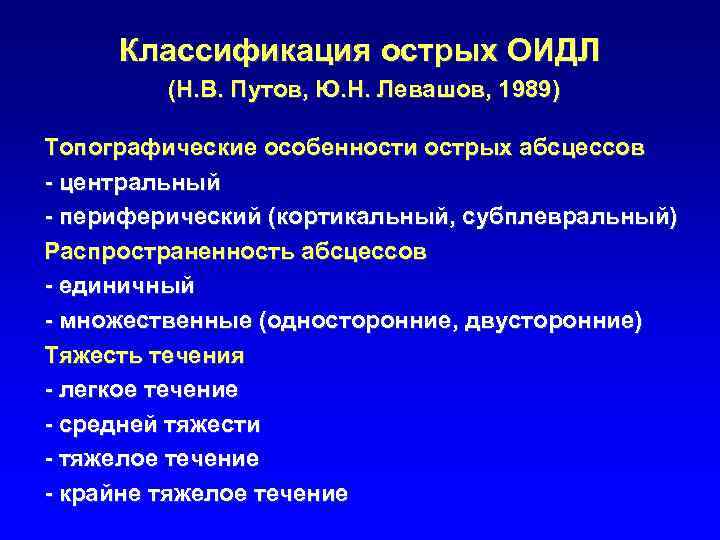

Классификация острых ОИДЛ (Н. В. Путов, Ю. Н. Левашов, 1989) Топографические особенности острых абсцессов - центральный - периферический (кортикальный, субплевральный) Распространенность абсцессов - единичный - множественные (односторонние, двусторонние) Тяжесть течения - легкое течение - средней тяжести - тяжелое течение - крайне тяжелое течение